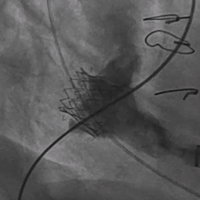

手术按照术前讨论方案进行,过程顺利,成功植入23号Renato®球扩瓣,瓣膜植入位置理想,启闭功能表现出色,左室造影及经食道超声反复观察无明显瓣中及瓣周反流。Renato球扩瓣植入后二尖瓣峰值流速降至1.37m/s,平均跨瓣压差降至3mmHg, 左室流出道峰值流速不到1.5m/s。术后患者即清醒,在手术间拔除气管插管,并送回心外科监护室,观察10余小时后,次日转回普通病房。

术前左室造影,可见二尖瓣瓣内大量反流 术后左室造影,无反流及瓣周漏